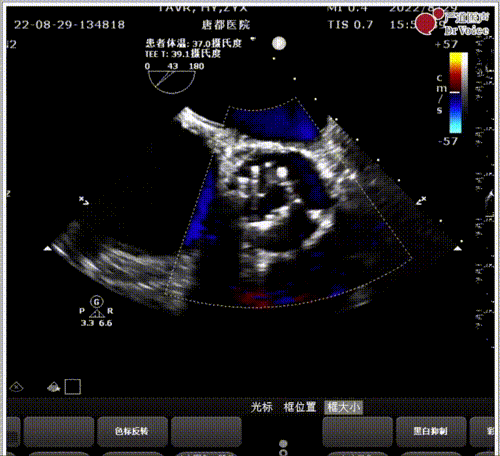

图8. 术中食道超声证实瓣架处于0位

即刻食道超声见瓣架展开充分,微量瓣周漏,平均跨瓣压差7mmHg。